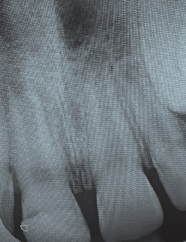

Die aufgrund einer infizierten oder nekrotischen Pulpa notwendige endodontische Behandlung, beispielsweise nach einem dentalen Trauma, kann durch ein weit offenes Foramen apikale bei einem noch im Wachstum befindlichen Zahn deutlich erschwert sein. Die noch dünnen und grazilen Dentinwände sowie das nicht abgeschlossene Längenwachstum führen zu einem ungünstigen Kronen-Wurzel-Verhältnis und zu einer erhöhten Frakturgefahr des betroffenen Zahnes (Abb. 3). Durch die bisherige Therapie, der Apexifikation, und der damit geschaffenen apikalen Barriere konnten zwar im Anschluss die notwendige endodontische Behandlung sowie Wurzelfüllung durchgeführt werden, das Frakturrisiko verringert sich jedoch nur minimal. Das Ziel ist es also, eine Therapiemöglichkeit zu schaffen, die sowohl ein Längen- und Dickenwachstum der Wurzel fördert als auch die Bildung eines physiologischen Apex induziert und damit die Prognose des Zahnes langfristig erhöht. Die regenerative Endodontie kann die weiterführende Entwicklung des Zahnes ermöglichen (Abb. 4). Voraussetzung für diese erfolgreiche Durchführung ist eine ausreichende Desinfektion, ein offenes Foramen apikale und ein nicht aufbereiteter Wurzelkanal.